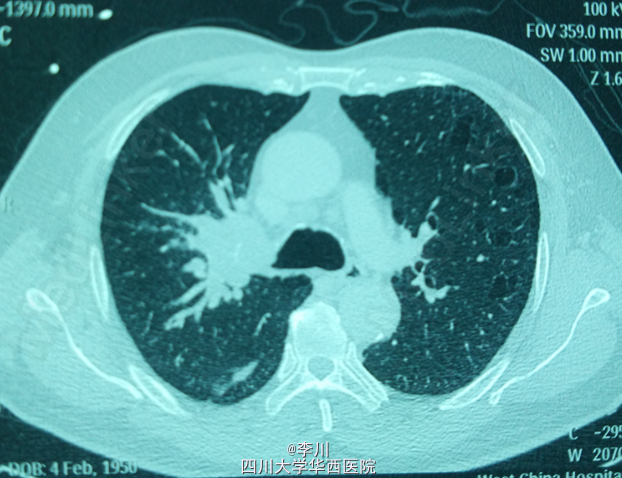

心肺腹查体无特殊异常。行胸部CT示:右主支气管内软组织影,大小约3.6*5.2cm,右上叶支气管开口变窄。纤支镜:右主支气管新生物,完全阻塞右肺上叶支气管;病理:查见鳞癌。

诊断为:右肺中央型鳞癌。于全麻下行右肺上叶切除+支气管袖式成形+系统淋巴结清扫术。术中见:肿块位于右肺上叶,约5cm大小,清扫2,4,7,10,11,12组淋巴结。手术过程顺利。